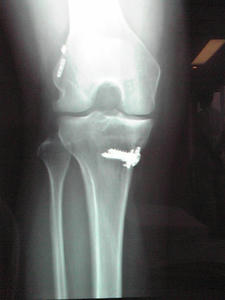

3年前に膝の靭帯が切れていたため手術をした。 私の膝にはボルトが入っていた。 抜かなくてもいいボルトだったけど、 当たると痛いこともあり、今回、 膝に入っていたボルトを抜く手術をしてきた。 無事に手術が終わってホントよかった。 それにしても、こんなんが体に入っていたとは・・・。コワッ。 入院前の検査の時に、看護師さんに 「これ読んどいてねー」と軽く渡された麻酔説明書を読んだあの日から、 不安と恐怖でいつも以上に眠れない日々の始まり。 以下、一部抜粋。 『安全を確保するべく万全の対策を講じていますが、医療行為は100%安全であるとは言えません。麻酔・手術中に予期せぬ偶発症が生じる可能性をご理解ください。これらの偶発症により死に至る可能性があります。』 100%じゃないのは重々承知のうえやけど、死に至る可能性ってどうなん?! めっちゃ怖いやん?! 過去に2回麻酔をしたことはあるけど、こんな説明書を読んだのは初めてだった。 先生曰く、1%でも可能性があることは書いとかないと、後で問題になるからとのこと。 確かに、それは納得。 今、うるさい人多いですもんね。ま、私もその一人ですけど。笑。 私はいい意味でも悪い意味でも、この世に『絶対』はないと思っているので、 毎晩いろんなことを考えた。ホントに。 当初、全身麻酔の予定だったが、手術前夜に、 先生から、明日は腰椎麻酔に変更してもいいかと言われ、 全身麻酔よりリスクは少ないと思っていたので、はい。と即答したけど、 病室に戻り、説明書を読むと全身麻酔と同じことが書いてあるうえに、 背骨に注射の文字。何?!背骨に注射?!ありえん!! えー、それやったら全身の方が断然いいやん!と思い、 速攻、先生のところに戻り、 『背骨に注射とかめっちゃ痛そうなんですけどー。全身の方がいいです。』と言うと、 『大丈夫や。痛さは人それぞれやし。1回経験してみー』と言われ、 経験ねぇー、そうよねぇ、こんな経験もうないかも。と思い、簡単に誘導され、承諾した。 経験やって言われるとやってみたくなる性分の私。 ま、この経験が今後、何かに生かされることはないような気がするけど・・・。 怖がっていたわりに連日の睡眠不足のせいで、物凄い睡魔に襲われ、 前日は就寝時間には寝てた。爆睡。 手術当日も、看護師さんに起こされるまで寝ていたので、 『あんた、度胸あるやないの!』と言われたぐらい、ここぞとばかりに寝てた。笑。 一応、緊張はしてた。 手術前日の夕食以降、絶飲絶食でしたが全くお腹が空かなかったし。 普段の私では考えられないことやしね。 まずは麻酔。 背骨の注射は今までされたどの注射よりも群を抜いて痛かった。 手術前に手の甲にされた点滴もたいがい痛かったけど、背骨は強烈だった。 『もっと背骨を丸めて小さくなって!もっと力抜いて!』 と、何回も言われたけど、体固いしもう限界やし、背中丸めて力抜くって難しいやろー。 力入るってー。 と、心の中で叫んでた。 麻酔の段階で汗だくになったし、結構な体力を消耗した感じだった。 手術室はクラッシック(←主治医の趣味らしい)が流れていて、 ドラマで見るシリアスな感じはまるでなく、雑談している中、手術が始まった。 軽っ!!って思ったけど、ま、簡単な手術やしね。 私も一緒にしゃべってた。 意識がある中での手術は何とも不思議な感じだった。 先生が実況してくれてたけど、下半身の感覚は全くないので、 自分の足を手術されてる感じはなく、平穏に時は流れてだけど、 ボルトを抜く時に、カンカンカンとトンカチで叩くような音が聞こえた時は、 脳まで振動が伝わったし、さすがに怖かったけどね。 手術時間は麻酔を含め約1時間。無事に終了。 予定よりちょっと終わるのが遅かったので、妹が心配してたけど、 笑顔で帰ってきた私を見て安心してた。 入院する度に思うけど、看護師って仕事はホントに大変やし、私にはできないな。 友達にも何人かいるけど、ホント脱帽もんやわ。 みんな優しかったし、おばちゃん看護師さんはかなりパワフルでおもしろかった。 入院中にすごくリラックスできたのも看護師さんのおかげだなと思った。 次に入院する時は、出産でしたいもんやわ。 いつになることやらって感じやけど・・・。 |